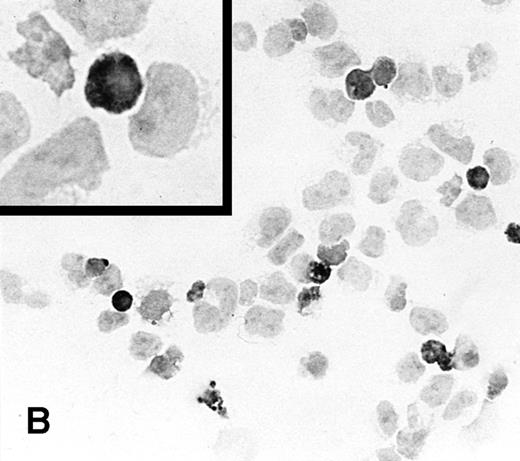

To determine the ability of an MuLV-based retroviral vector to stably infect NK cells, expression of IL-2 and Neo markers was evaluated. The efficiency of a flow-through method was determined by immunostaining for expression of the transgene. As a control, MFG-IRAP–infected NK-92 cells were used. Figure 1 shows staining for IL-2 of cultured P-NK-92 cells, which were negative for intracytoplasmic IL-2, and of transiently transduced NK-92 cells, which contained 10% to 20% stained cells. The percentage range of positive cells was determined by counting a total of 200 cells on each immunostained cytosmear prepared from three different cultures of transiently transduced NK-92 cells. These cultures were not tested by ELISA for the level of IL-2 in the supernatants because of the presence of exogenous IL-2. Instead, a culture of NK-92 cells transduced with the IRAP gene and containing 2% to 3% IRAP-positive cells by immunostaining (not shown) was tested in ELISA for the level of IRAP in the supernatant. At 72 hours posttransduction, the supernatant contained 8.4 ng IRAP/106 cells/48 h. P-NK-92 cells did not produce IRAP.

Immunostaining for IL-2 in transduced but nonselected NK-92 cells. (A) P-NK-92 cells incubated for 48 hours in the absence of exogenous IL-2 prior to staining. (B) Transduced nonselected (48 hours posttransduction) IL-2/Neo/NK-92 cells incubated for 48 hours in the absence of exogenous IL-2 prior to staining. Insert shows an IL-2–expressing NK cell (original magnification ×1,000). The staining reaction was developed with AEC, and the cells were counterstained with hematoxylin. For A and B, original magnification is ×500.